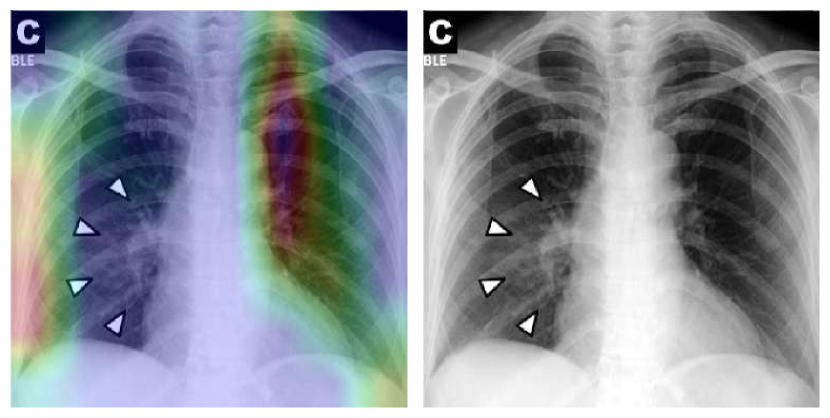

To overcome the aforementioned issues and force the model’s attention to the correct regions of interest (ROIs), we introduce the COVID-CXNet. Our model is initialized with the pretrained weights from CheXNet. A dataset of 3,628 images, 3,200 normal CXRs and 428 COVID-19 CXRs, are divided into 80% as training-set and 20% as test-set. Batch size is set to 16, rather than 32 in previous models, regarding memory constraints. Grad-CAMs of the COVID-CXNet for random images are plotted in Fig. 15.

Refer to caption

Figure 15: Grad-CAM visualization of the proposed model over sample cases

More Grad-CAMs are available in Appendix A. Heatmaps are more accurate than previous models, while an accuracy of 99.04% and an f-score of 0.96 are achieved. Table 3 is the confusion matrix of the proposed model.

Proposed CheXNet-based model is capable of correctly classifying images. In many cases, it can localize pneumonia findings more precisely than the CheXNet. An example is illustrated in Fig. 16.

(a)

(b)

(c)

Figure 16: Comparison between the CheXNet and the proposed model; (a) is the image with patchy opacities in the upper left zone, (b) and (c) are heatmaps of the CheXNet and the proposed COVID-CXNet, respectively.

Fig. 16 shows a CXR with an infiltrate in the upper lobe of the left hemithorax [47]; while CheXNet missed the region of pneumonia, the proposed model correctly uncovered the infiltration area. One concern about COVID-CXNet results is that it has pointed into other irrelevant regions, even outside the lungs. The same problem happens when there are frequently-appeared texts and signs, such as dates, present in the image. Fig. 17 shows how text removal can improve model efficiency.